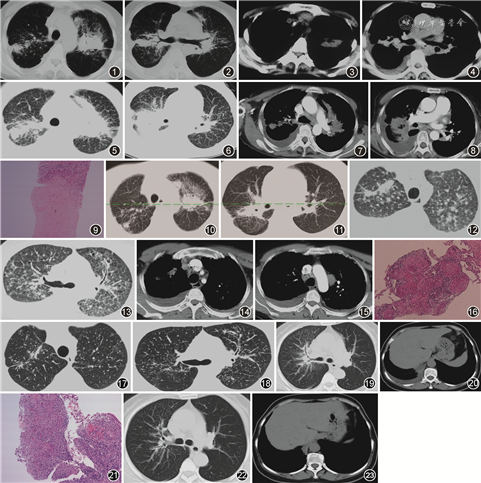

例1 女,51岁。2016年12月因“间断咳嗽伴胸闷2年”于当地医院行胸部CT(图1, 2, 3, 4),提示双肺弥漫性病变伴右侧胸腔积液,抗感染治疗无好转。2017年2月转诊至上级医院住院,行血常规、肝肾功能、ESR、C反应蛋白及肿瘤标志物等检查结果未见异常,结核菌素斑点试验(T-SPOT)阴性。胸腔积液检查:李凡他试验阳性,细胞数为2 600×106/L,淋巴细胞比例为82%,总蛋白为48.3 g/L,腺苷脱氨酶(ADA)为24.5 U/L,乳酸脱氢酶(LDH)为192 U/L,细胞学检测见部分淋巴细胞,少量间皮细胞。心电图及心脏彩色多普勒超声结果未见异常。支气管镜显示支气管慢性炎症,于左肺上叶固有支黏膜浸润处取活检,病理学检查可见镜下支气管黏膜组织呈慢性炎症改变,伴小肉芽肿形成及坏死,抗酸染色阴性。胸腔镜显示胸腔内壁层胸膜广泛充血,表面较多白色膜样物质附着。胸膜活检病理学检查见增生的间皮细胞、间质内见炎症细胞浸润,另见少量纤维结缔组织及血细胞。临床诊断肺结核并右侧结核性胸膜炎,于2017年3月开始给予4HRZE/9HRE(H:异烟肼,R:利福平,Z:吡嗪酰胺,E:乙胺丁醇)抗结核治疗。2018年4月12日复查胸部CT(图5, 6, 7, 8)发现病灶增多,为进一步诊治入院。入院复查T-SPOT及PPD均为阴性。血管紧张素转化酶(ACE)为52 U/L。胸部CT引导下右上肺病变经皮肺穿刺活检病理(图9)见肉芽肿性炎伴凝固性坏死,倾向结核性肉芽肿。病理组织抗酸染色阴性、过碘酸雪夫染色阴性、六胺银阴性、结核分枝杆菌DNA-PCR(TB-DNA)阴性、Xpert MTB/RIF阴性。经院内多学科会诊诊断为结节病(累及肺、支气管、胸内淋巴结、胸膜),建议完善全身正电子发射计算机断层显像(PET/CT)评估其他器官受累情况,患者拒绝。给予泼尼松40 mg/d,治疗1个月后于2018年6月12日复查胸部CT(图10,11)病灶明显吸收,糖皮质激素(激素)逐步减量,半年后停用,目前随访未复发。

例2 男,41岁。2009年因双肺弥漫性病变于外院诊断为菌阴肺结核,给予规则抗结核治疗1年停药,当时PPD阴性。2018年7月因“咳嗽伴右侧胸痛2个月”于当地医院住院,胸部CT(图12, 13, 14, 15)提示双肺弥漫性结节伴右侧胸腔积液,左侧胸腔少量积液。右侧胸腔积液检查:李凡他试验阳性,细胞数为900×106/L,淋巴细胞比例为80%,总蛋白为38.1 g/L,ADA为17.7 U/L,LDH为103 U/L,细胞学检测见部分淋巴细胞,少量间皮细胞。T-SPOT阴性,肿瘤标志物未见异常。心电图及心脏彩色多普勒超声未见异常。临床诊断为结核性胸膜炎,给予HRZE抗结核治疗1个月,右侧胸腔积液无好转,转诊入院。入院后于胸部CT引导下行右上肺经皮肺穿刺,病理学检查(图16)提示非坏死性上皮样肉芽肿性炎,抗酸染色阴性,TB-DNA阴性,Xpert MTB/RIF阴性。血ACE为66 U/L。临床诊断为胸膜肺结节病,建议完善全身PET/CT评估其他器官受累情况,患者拒绝。给予泼尼松40 mg/d,治疗2个月后于2018年9月26日复查胸部CT(图17,18)可见病灶明显吸收,激素逐步减量,半年后停用,目前随访未复发。

例3 女,50岁。2017年5月因“干咳2个月”于当地医院行胸部CT(图19,20),提示双肺弥漫性病变伴纵隔淋巴结肿大及右侧胸腔积液。给予头孢他啶抗感染10 d无好转。实验室检查提示血常规、尿常规、肝肾功能电解质及肿瘤标志物均未见异常,T-SPOT阴性。心电图及心脏彩色多普勒超声未见异常。胸腔积液检查:李凡他试验阳性,细胞数为1 600×106/L,淋巴细胞比例为85%,总蛋白为45.2 g/L, ADA为21.6 U/L,LDH为253 U/L,细胞学检测见多量淋巴细胞。支气管镜所见各叶段支气管无异常。于右下叶基底支行经支气管镜肺活检,病理学检查(图21)提示肉芽肿性炎,未见坏死,抗酸染色阴性,TB-DNA阴性,临床诊断为肺结核并右侧结核性胸膜炎,给予HRZE抗结核治疗1个月,复查无好转,转入本院。入院后查血ACE为77 U/L,结合患者影像学特点、病理提示非坏死性肉芽肿性炎、结核免疫学及微生物学阴性以及抗结核治疗无效的特点,临床更正诊断为胸膜肺结节病,建议完善全身PET/CT评估其他器官受累情况,患者拒绝。给予泼尼松30 mg/d,治疗1个月后复查胸部CT(图22,23)病灶明显吸收,胸腔积液吸收,激素逐步减量,半年后停用,目前随访未复发。